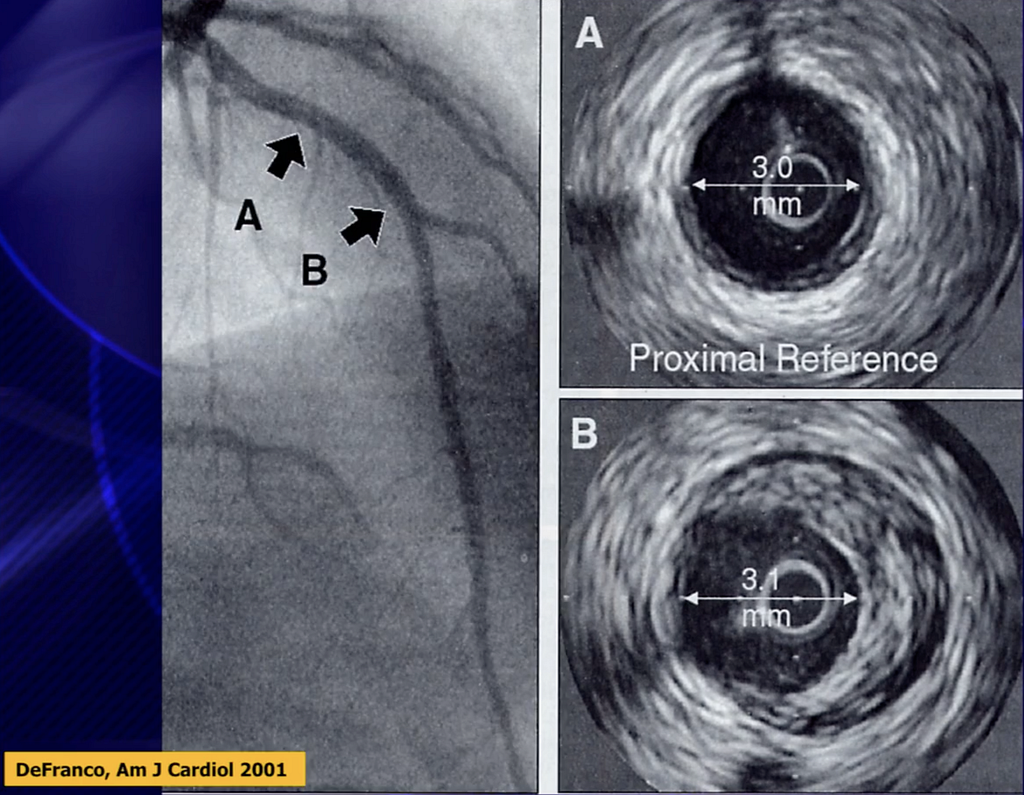

- Fig.6表示Plaque往vessel wall增長(outward bulging) > 往血管管徑內增長 →所以做CAG時,可能顯示通暢,但事實上已經有significant CAD出現 →所以會有false-negative angiography出現

- Fig.7顯示圖A與B在CAG下幾乎都顯示是通的(血管管徑差不多),但事實上使用intravascular US(IVUS)來看,發現B的位置其實有很大的plaque,但因為remodeling,所以管徑看起來還夠大,但其實rupture風險高。

- B的狹窄程度>A( B如果沒有使用IVUS來看,只會覺得似乎是通的,但事實上已經是處於狹窄狀態 )